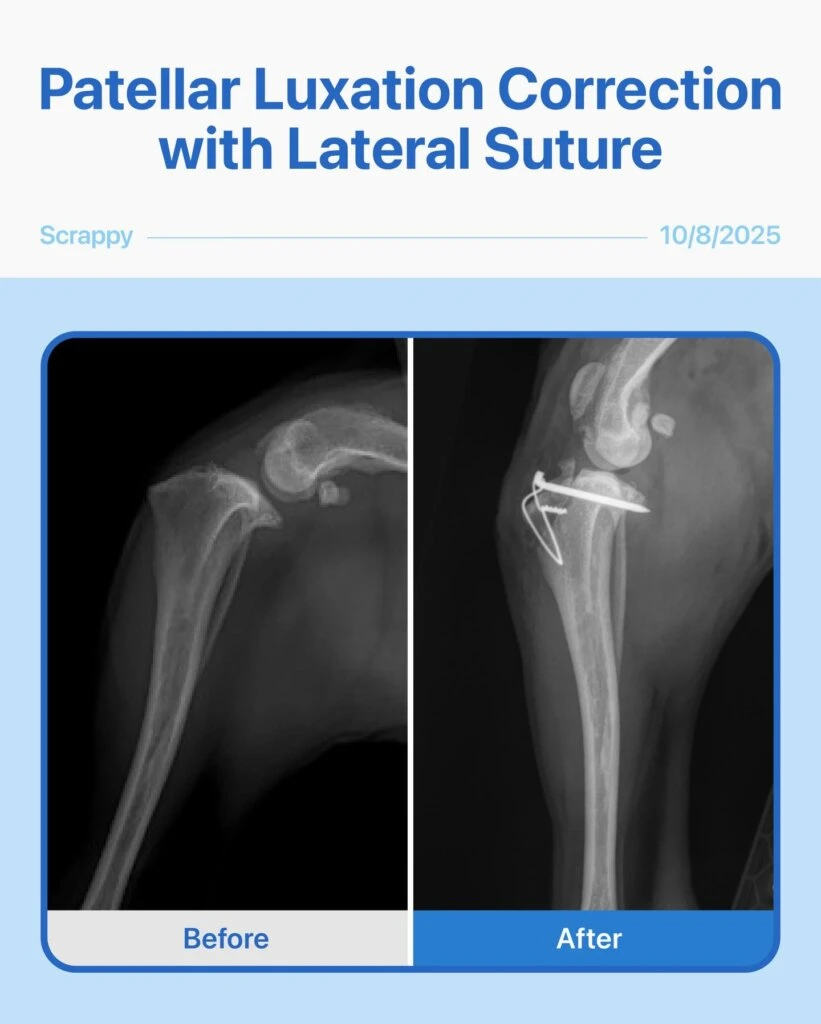

This brave 11-year-old Chihuahua mix came in after his owner noticed his knee kept dislocating. Radiographs showed a severe Grade 4 patellar luxation and a torn cruciate ligament.

Given his age, size, and breed, combining patellar luxation correction with lateral suture surgery was the safest and most effective option for him.